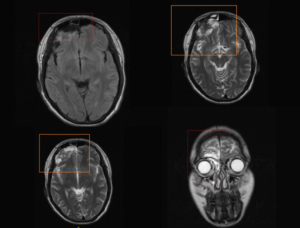

Картина арахноидальных изменений ликворокистозного характера в ходе исследований МР и КТ показывает наличие очагов с плотностью цереброспинальной жидкости, что подтверждает кистозную, неопухолевую природу образования.

На МРТ головного мозга арахноидит чаще всего не имеет достоверных признаков, но иногда может приводить к формированию кист, расположенных в субарахноидальном пространстве, то есть между мозгом и костью черепа. Это так называемые арахноидальные кисты. Арахноидальные кисты имеют четкие признаки на МРТ. Но, к сожалению, чаще всего мы не можем сказать, возникли эти кисты вследствие арахноидита, или они имеют врожденный характер. Поэтому в современной неврологии понятия «арахноидит» и «арахноидальная киста» различаются, и путать их не стоит.

Чаще всего диагноз «арахноидальные изменения ликворокистозного характера» пишется тогда, когда на МРТ достоверно не видно никаких кист, а имеется просто неравномерное расширение субарахноидального пространства, то есть увеличение количества спинномозговой жидкости (ликвора) между мозгом и костью черепа.

Основным методом ее диагностики является МРТ. На снимках арахноидальные изменения ликворокистозного характера выглядят как образования темного цвета, с четко ограниченными контурами, чаще всего округлой формы.